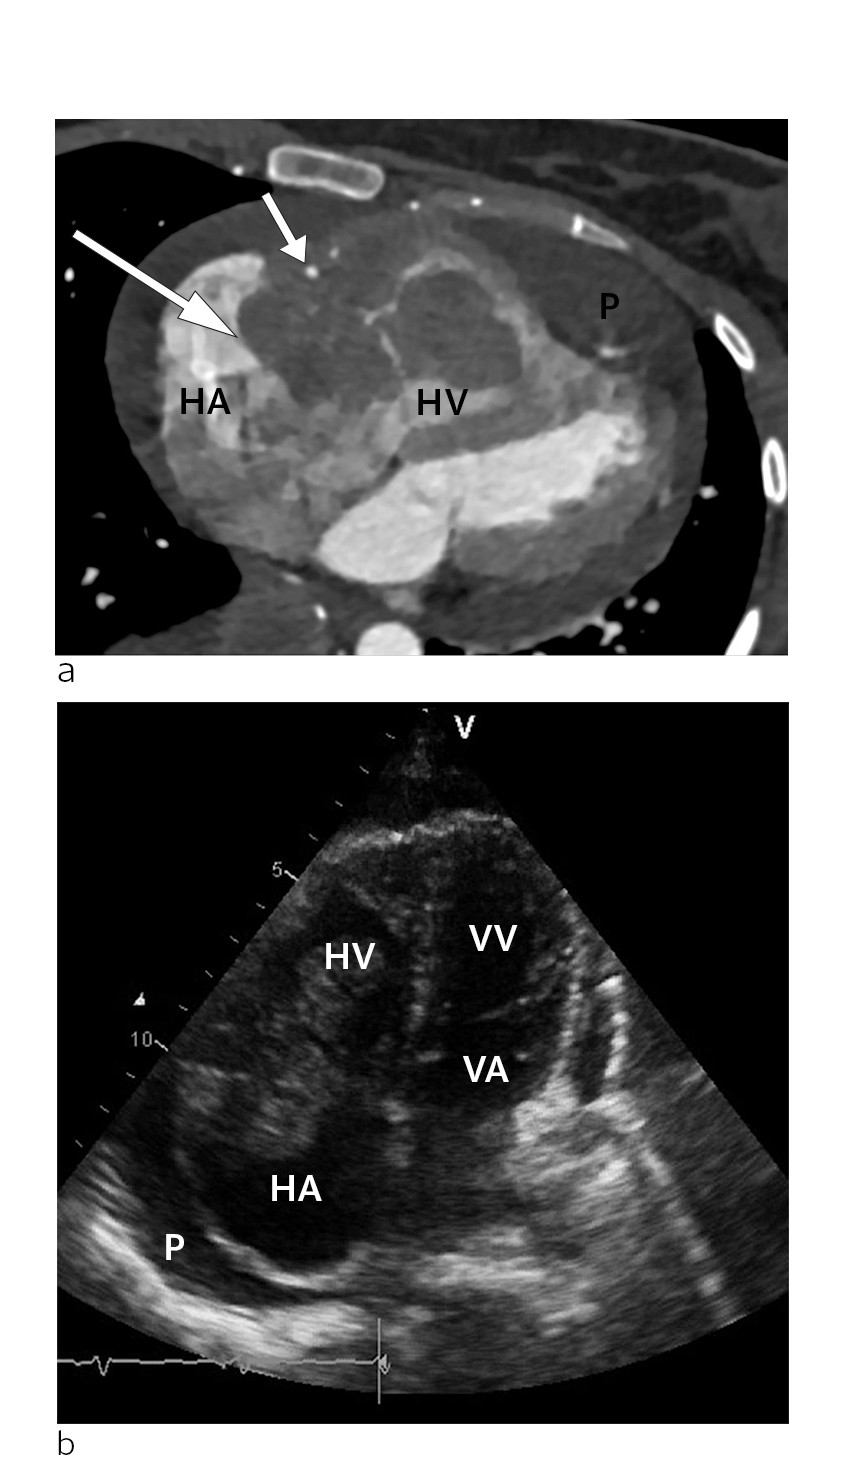

There was clear obstruction of normal blood flow in the tricuspid ostium. Pericardial effusion was also seen, particularly along the right ventricle, with a maximum size of 1.5 cm but no evidence of tamponade. The mitral and aortic valves on the left side of the heart appeared normal. The findings were confirmed with a cardiac CT scan, which also raised suspicion of infiltration of tumour masses into the right ventricular wall and pericardium (Fig. 1).

Figure 1 a) CT scan of the heart in the transverse plane at the time of diagnosis. Tumour (large arrow) in the right…

Figure 1 a) CT scan of the heart in the transverse plane at the time of diagnosis. Tumour (large arrow) in the right atrioventricular groove, surrounding an open right coronary artery (small arrow). The mass is located within the right atrium (HA) and right ventricle (HV). The tumour is also infiltrating the free wall of the right ventricle (HV). Pericardial effusion (P) can be seen around the heart, and is most pronounced apically. B) Echocardiogram at the time of diagnosis. Apical four chamber view showing the right atrium (HA), right ventricle (HV), left atrium (VA) and left ventricle (VV). The tumour is located at the transition between the right atrium and right ventricle, where it almost completely occludes the tricuspid ostium. Pericardial effusion (P) can be seen around the heart.